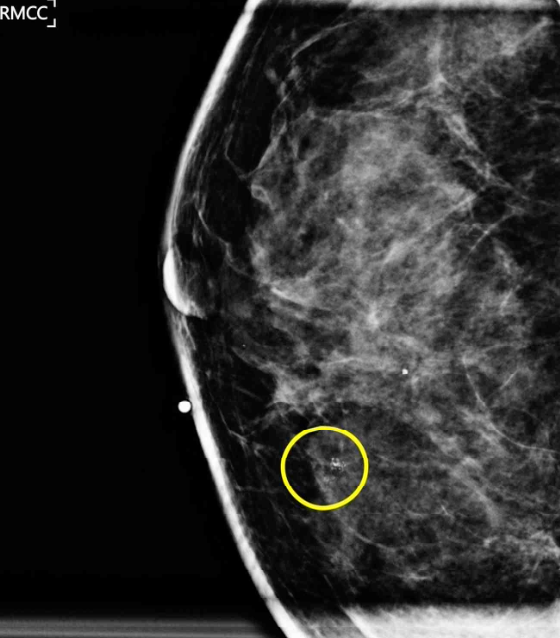

40세 여자가 유방암 검진에서 오른쪽 유방에 미세한 석회음영이 보인다고 병원에 왔다. 3년 전에 받은 유방 검진에서는 이상이 없었다고 한다. 혈압 125/85 mmHg, 맥박 60회/분, 호흡 12회/분, 체온 36.4°C이다. 오른쪽 유방에서 만져지는 덩이는 없다. 유방초음파에서 오른쪽 유방의 미세한 석회음영과 일치하는 1cm 크기의 병변을 확인하였다. 유방확대촬영 사진이다. 초음파 유도 중심부바늘생검 검체촬영에서 미세한 석회가 확인되었다. 유방조직검사 결과는 다음과 같다. 조치는?

MAM: grouped, fine pleomorphic calcification in Rt. breast

• MAM상 grouped, fine pleomorphic calcification이 확인되므로 악성 종양에 대한 감별이 필요하며, 이는 조직검사를 통해 이루어진다.

• 해당 증례에서는 초음파로 MAM의 미세석회음영과 일치하는 병변을 확인할 수 있었으므로 US-guided core needle biopsy로 조직검사를 시행하였다. 검체에서 미세한 석회가 확인되었다는 언급으로 보아 targeted lesion을 적절하게 획득한 것으로 판단할 수 있다.

• 해당 MAM에서 확인되는 석회화 및 병변의 양상을 고려할 때, 영상학적으로는 악성이 의심되어 BI-RADS 4a~4b 범주에 해당한다고 볼 수 있다. 현재 조직검사 결과는 양성 종양인 섬유샘종으로 나타났으므로, imaging-histologic correlation을 고려할 때 양성 결과와 영상 소견이 불일치(discordant benign)하므로 재검을 고려하는 것은 타당하다. 최초 조직검사는 중심침생검으로 시행되었으므로, 재검 시에는 충분한 조직 채취가 가능한 다음 단계의 생검 방법인 수술적 생검(예: 절제 생검 등)을 선택해야 한다. 그러나 해당 선택지에는 이를 반영한 옵션이 없는 것으로 보인다. Imaging-histologic correlation을 판단하기 위해서는 단일한 악성 의심 소견만을 기준으로 판단하는 것이 아니라, BI-RADS 분류를 기반으로 한 정확한 영상학적 평가가 필요하다. 다만 본 문제에서는 BI-RADS 분류가 제시되지 않은 바, 학부 수준에서 MAM/US 사진만으로 BI-RADS 카테고리를 정확히 판단하여 진단 알고리즘을 고려하는 것은 국시의 출제 의도와 맞지 않는 것으로 보인다. 따라서 본 문제는 재검을 요하는 경우 충분한 조직 채취가 가능한, 다음 단계의 생검 방법(1st core needle Bx → 2nd surgical Bx)을 택해야 한다 정도의 지식으로 해결하는 것이 적절할 것으로 판단된다.